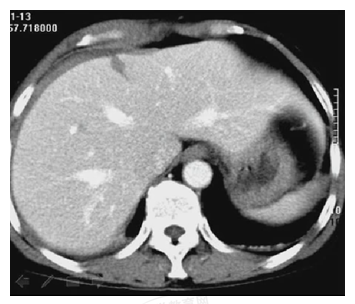

患者,女性,20歲。胸腹部被車撞傷5小時(shí)。診斷為

A.肝破裂

B.脾破裂

C.肝脾破裂

D.肝腎挫裂傷

E.腎損傷

【答案】A